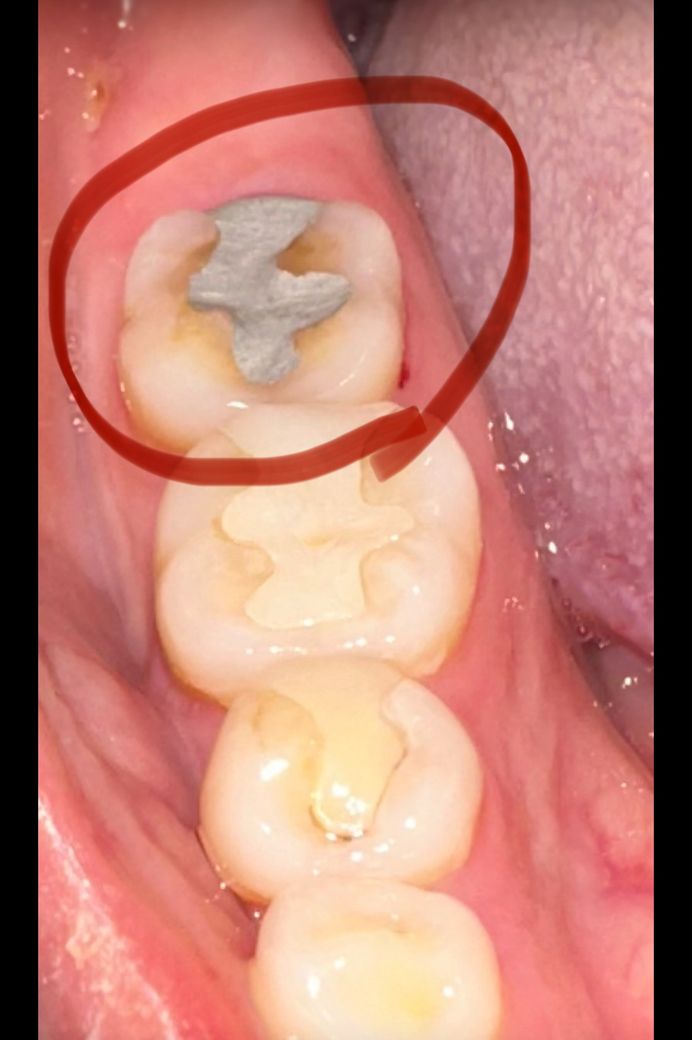

아말감으로 떼운 후 통증 관련 질문 드려요 전문가분들 답변 부탁드립니다

아래쪽 어금니 금으로 떼웠는데 2번 정도 떨어지고 다시 붙이고 1년만에 떨어져서 8월 6일날 기존에 다녔던 치과 말고 다른 치과 방문 하였어요 다시 붙일려니 안맞아서 오래된 치과라 보험 적용 되는 아말감으로 떼워주셨습니다 이빨을 긁어내서 그런지 씹을때 통증 심하고 바로 위에 윗 어금니가 크라운으로 덮어 씌웠는데 그거랑 부딪혀서 그러는건지 말 하다가도 부딪히면 찌릿 합니다 이빨을 긁어내서 이런건가요? 조금 더 지켜봐도 괜찮은걸까요? ㅠㅠ 이틀 지났지만 여전히 통증은 씹을때 심하네요.. 말도 안하고 가만히 있으면 안아픕니다 눌러보면 아프기도 해요 전문가분들 도와주세요

• 1번 째 사진

1. 갈바닉 반응 문제

2. 치아 크랙

3. 깊은 충치로 인한 치수염